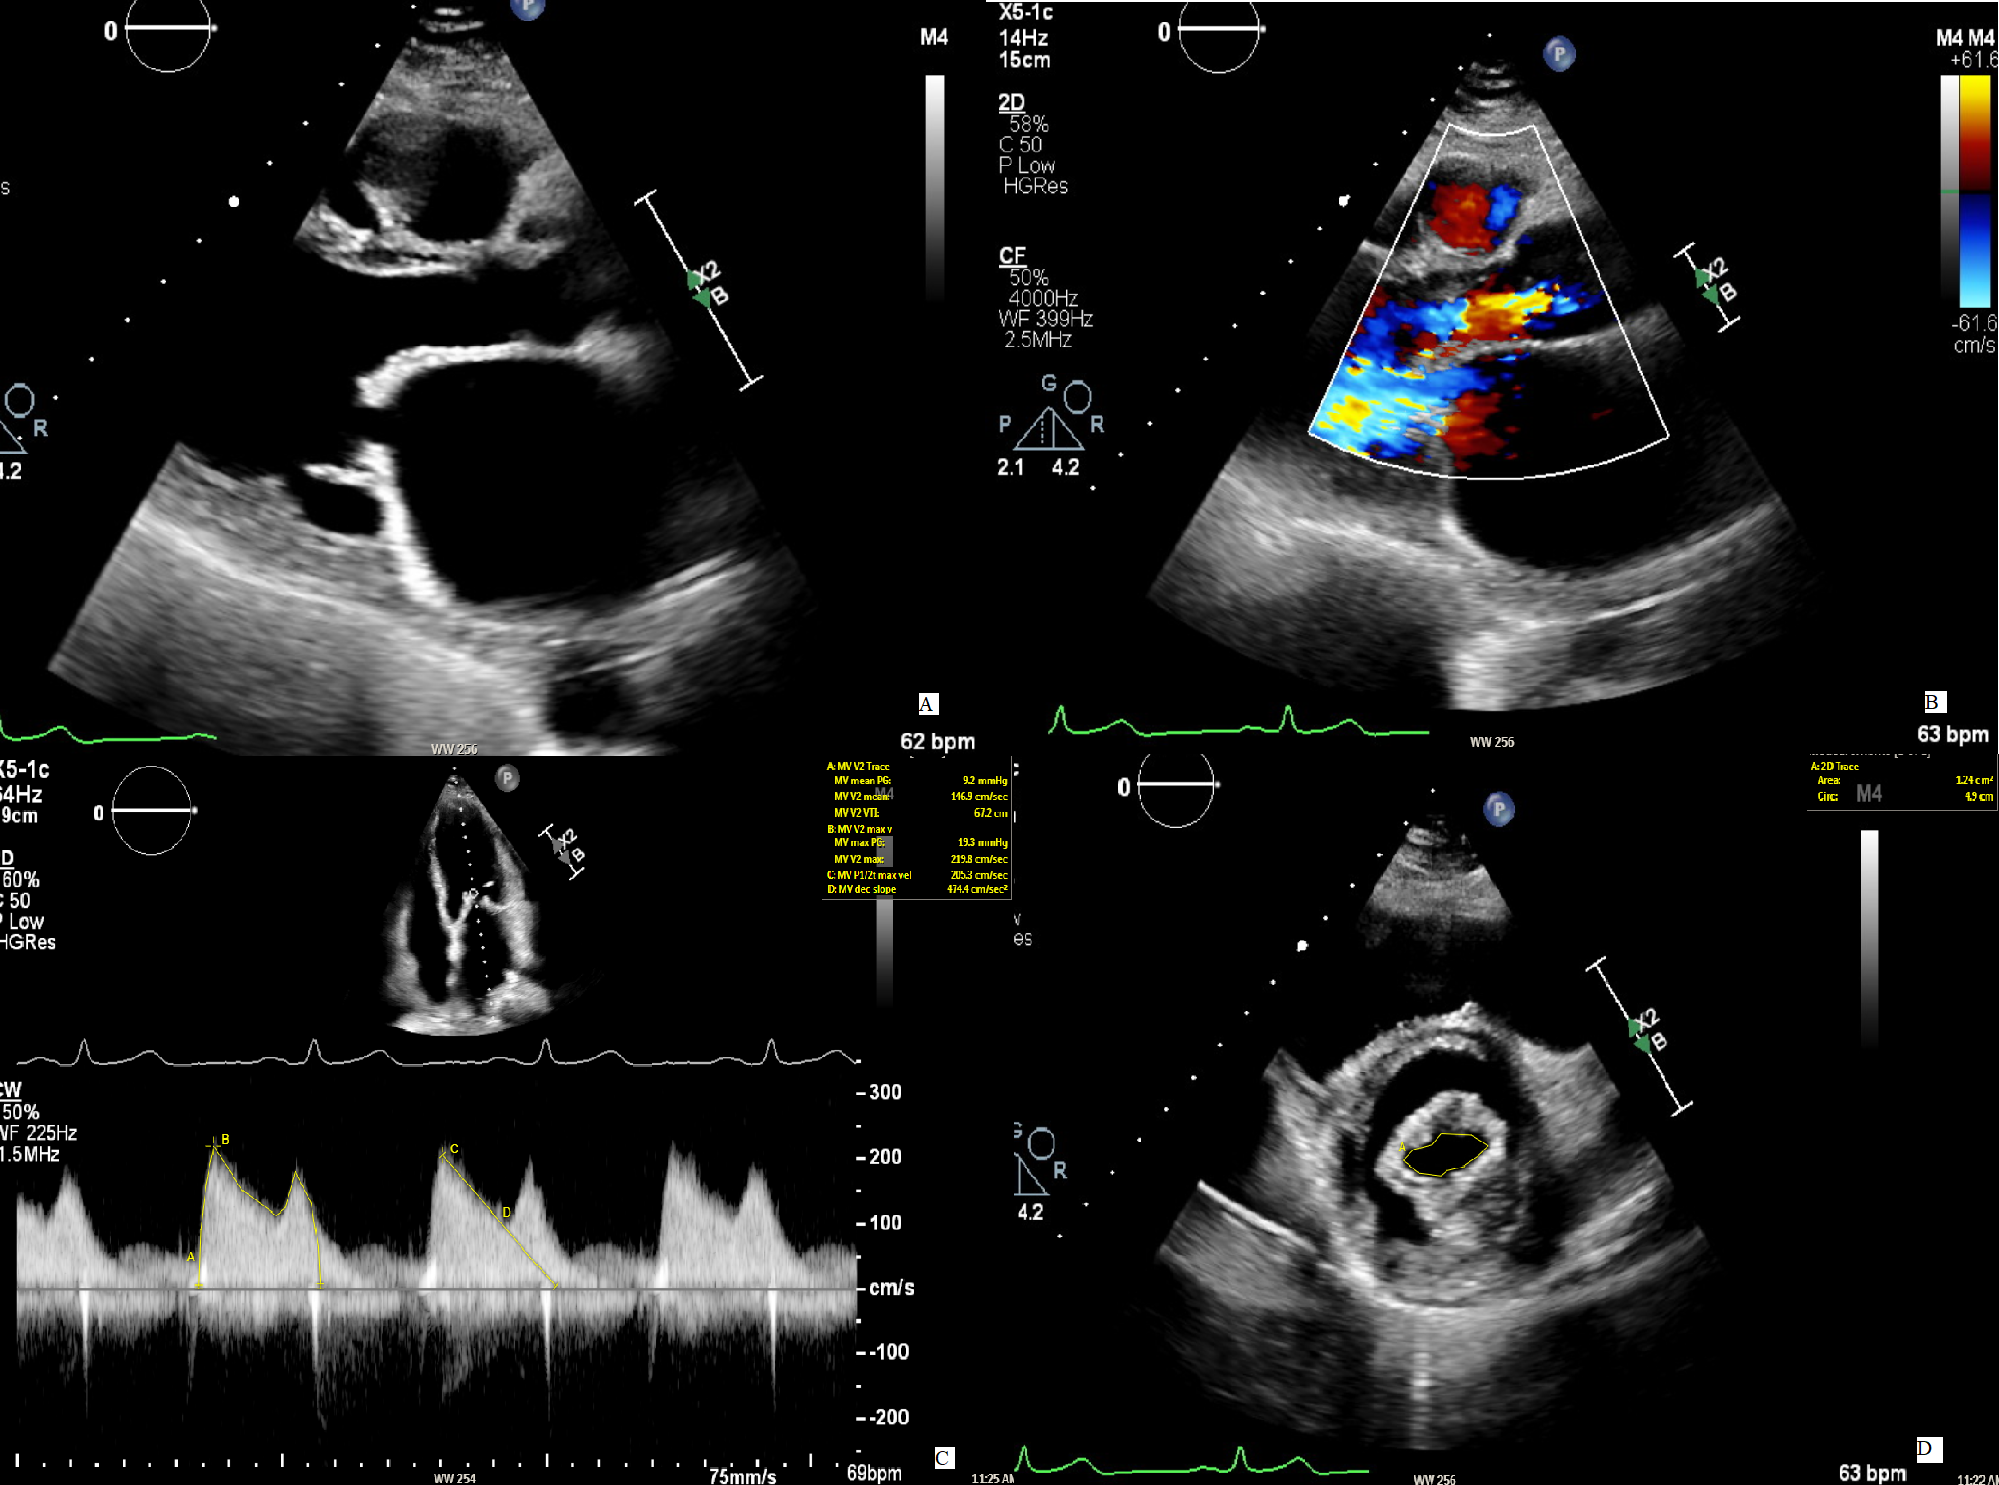

Fig. 4.

Fig. 4.Aortic flow quantification on cardiac magnetic resonance phase contrast imaging. Flow quantification in the ascending aorta allows for quantification of forward volume, regurgitant volume and regurgitant fraction irrespective of the presence of other combined valvulopathies. In the image, a patient with both aortic and mitral regurgitation and left ventricle dilation underwent cardiac magnetic resonance in order to determine the severity of the main lesion, being the aortic regurgitation. The analysis revealed a regurgitant fraction of 42%, compatible with a significant aortic regurgitation.